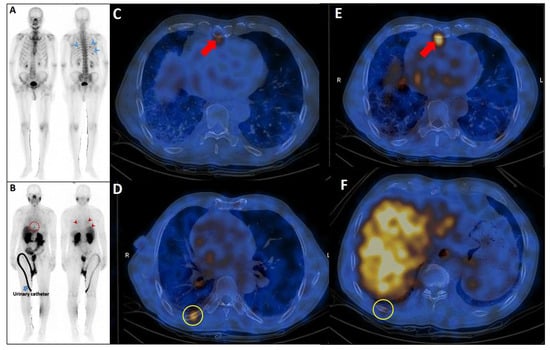

Pleuro-Pulmonary Extramedullary Plasmacytomas in Multiple Myeloma: A 15-Year Experience from a Tertiary Center

Background/Objectives: Extramedullary involvement in multiple myeloma represents an aggressive disease phenotype, associated with reduced survival and an unfavorable prognosis. Thoracic manifestations are rare and remain poorly characterized in the literature. Methods: We conducted a retrospective, single-center study at the Fundeni Clinical Institute, including patients diagnosed with multiple myeloma between February 2010 and February 2025. The study cohort consisted of 34 patients with infiltration of the pulmonary parenchyma, pleura, or the presence of myelomatous pleural effusion. Diagnosis was confirmed using a combination of imaging modalities (computed tomography or magnetic resonance imaging), cytological examination, immunophenotyping, and histopathological confirmation whenever feasible. Results: Out of a total of 2012 patients with multiple myeloma, the incidence of pleuro-pulmonary extramedullary involvement was 1.6%. The median age at diagnosis was 58 years. Pleuro-pulmonary disease was present at initial diagnosis in 26.5% of cases, while 73.5% developed it at relapse. The most common presentation involved combined pleural involvement and myelomatous effusion (70.6%). Adverse prognostic markers included elevated β2-microglobulin levels (in over 80% of cases) and increased lactate dehydrogenase (LDH) in approximately 50%. Cytogenetic abnormalities such as del(17p), t(4;14), t(14;16), t(11;14), and 1q gain were identified. The median overall survival (OS) from the diagnosis of pleuro-pulmonary extramedullary disease was 16 months, with a 2-year survival rate of 25%. No patient survived beyond 5 years. The median progression-free survival (PFS) was 9 months. Conclusions: Our findings confirm the aggressive clinical course and poor prognosis of these disease manifestations, mainly when they occur at relapse. In the absence of standardized treatment guidelines, individualizing therapy and accessing novel strategies may be essential for improving patient survival.